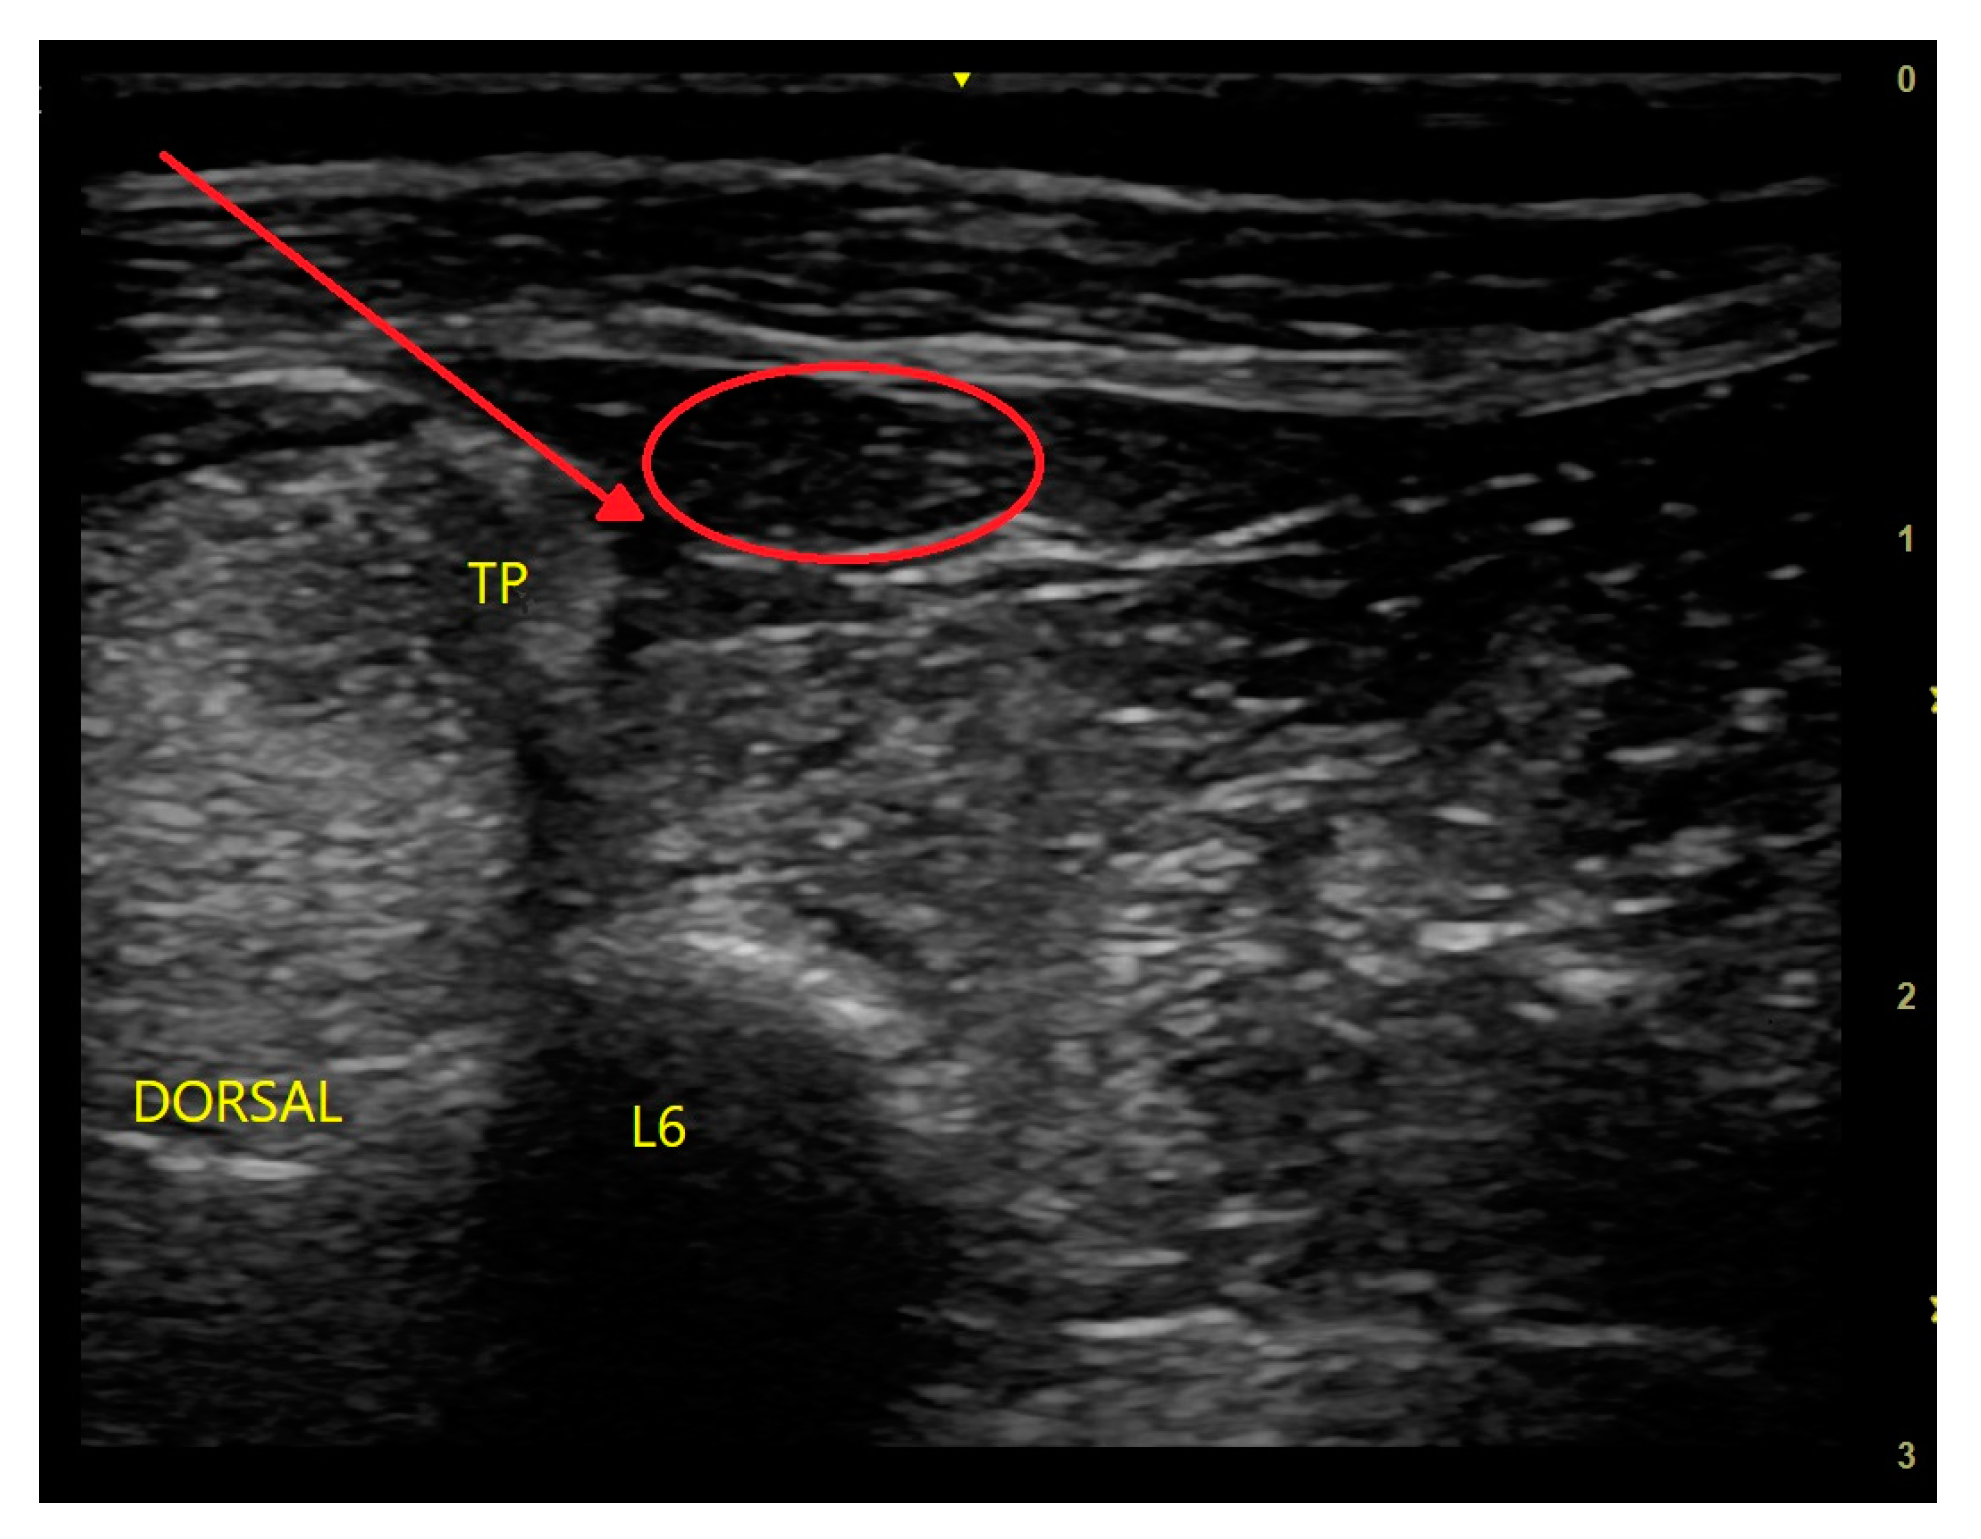

10.1. Quadratus Lumborum Block (QLB)